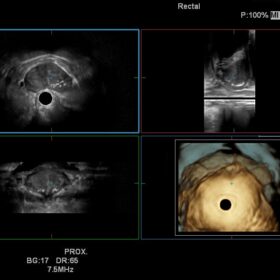

Ultrasound Noblus – Image Gallery and Videos

The Noblus offers premium modalities that can be exploited in many different clinical situations. Although compact in design, the powerful engine of the Noblus enables functions such as Real-time Tissue Elastography (RTE), dynamic Contrast Harmonic Imaging (dCHI), real-time 3D with STIC (Spatio-temporal Image Correlation) option and CW Doppler, features previously found only on larger cart-based systems.